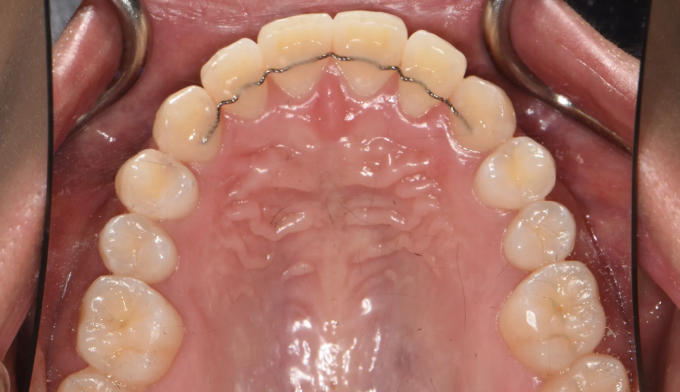

총 치료기간은 15개월 소요되었습니다.

거꾸로 물려있던 앞니를 앞으로 보내면서, 아래치열은 사랑니발치 후 미니스크류를 이용하여 후방이동시켰습니다.